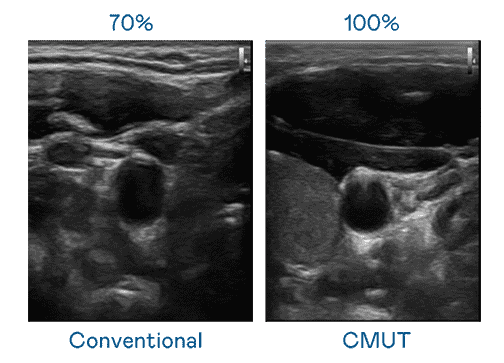

CMUT 技术是一种用电容式微机电元件来产生超音波讯号的技术。。。。与传统 PZT 压电式技术相比,,CMUT 频宽增加 30%,,,更宽频的超音波讯号让影像解析度大幅提升,,是实现高影像品质医疗超音波扫描、、促进精准医疗发展的关键技术。。。。

超音波影像的解析度高低,,,首先取决于探头能发出的讯号频宽。。。。28国际 CMUT 可提供高清晰的超音波讯号,,提供高频宽、、高灵敏度、、、、影像纹理细节更高的超音波影像,,协助医护人员缩短影像判读时间及利用精准的医疗影像进行诊断。。。